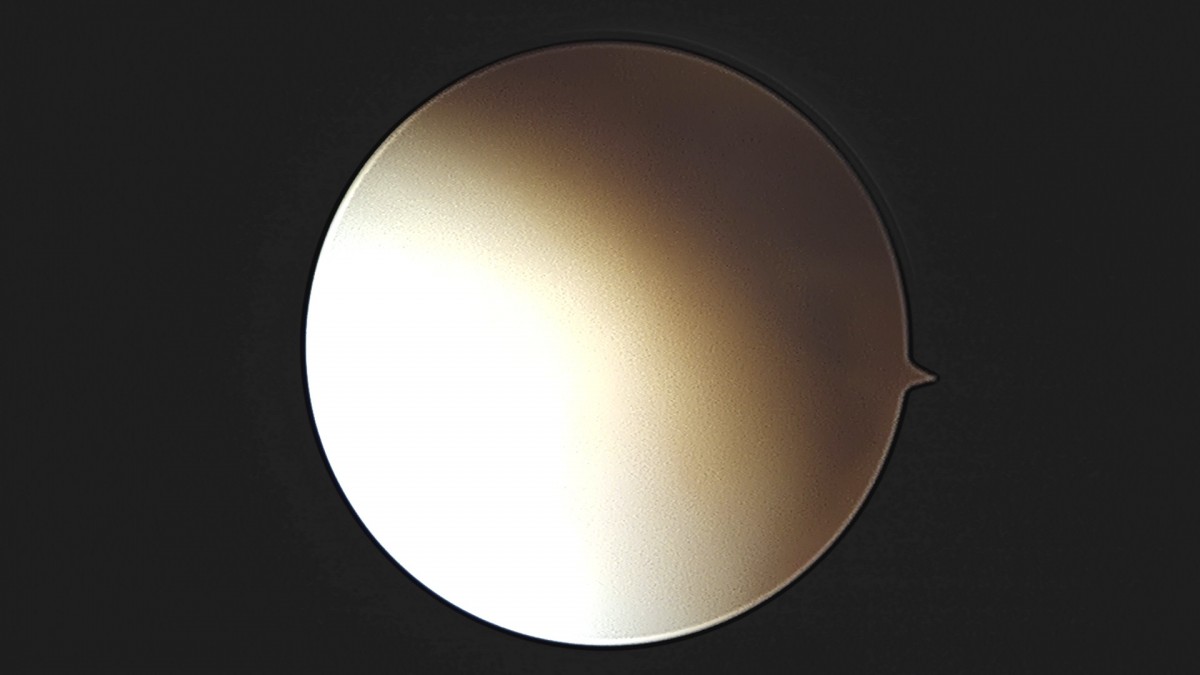

이재상원장님 발목 인대 봉합술 박찬O 환자

dae765e4d9ac96aee867c9d6292d8784_1758007285_0376.jpg